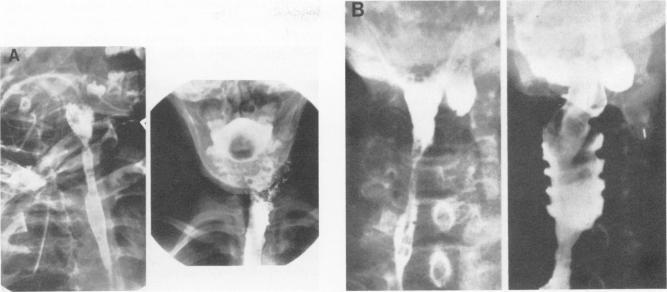

Fifty-five patients with disorders of the pharynx or cervical esophagus requiring extensive ablative therapy were reconstructed by heterotopic autotransplantation of a segment of jejunum. Of these 55 patients, the overwhelming majority were treated for squamous cell carcinoma or the complications of combined radiation and operative therapy. There were six graft failures in the entire group of 55 patients for a transfer reliability of 90%. Three patients died in the perioperative period (5%). The purpose of this paper is to report on the treatment of a subset of these patients in whom fixed cicatricial stenosis of the gullet was the problem or in whom a radionecrotic cutaneous fistula existed. Fourteen such patients were treated, ten with stricture and four with fistula. Both patch grafts of on-lay segments and more routine circumferentially intact tubed segments of jejunum were used depending upon the nature of the defect. The youngest patient in this group was a 3-year-old juvenile diabetic with caustic stricture and the oldest was a 75-year-old man with fixed stricture following operation and radiation for cancer. Nine of ten and four of four anatomic reconstructions were successful in the stricture and fistula patients, respectively. All of these 13 patients with a neo- gullet of jejunum were able to handle secretions and liquids satisfactorily. Eleven patients were on a regular diet and had no discernible physiological impairment in alimentation. One patient had mild dysphagia and used a blenderized diet. One patient was able to swallow liquids only. In this patient the resection for tumor was so high and so extensive that the physiologic act of deglutition itself was impaired. There were no perioperative deaths, although one patient has succumbed to recurrent and metastatic carcinoma. When conventional treatment for stricture or fistula in the cervical alimentary tract has failed, reconstruction can be accomplished safely by free revascularized jejunal graft. Successful alimentation can be anticipated in all patients in whom the physiologic mechanism of deglutition itself is not drastically impaired.

55例患有咽或颈段食管疾病且需要广泛切除治疗的患者,通过空肠段异位自体移植进行了重建。在这55例患者中,绝大多数接受的是鳞状细胞癌或放疗与手术联合治疗的并发症的治疗。55例患者中共有6例移植失败,移植成功率为90%。3例患者在围手术期死亡(5%)。本文的目的是报告对这些患者中的一部分患者的治疗情况,这些患者存在食管固定性瘢痕狭窄问题或存在放射性坏死性皮肤瘘。治疗了14例这样的患者,其中10例为狭窄患者,4例为瘘患者。根据缺损的性质,既使用了补片移植的外置空肠段,也使用了更常规的完整环形带蒂空肠段。该组中最年轻的患者是一名3岁的患有腐蚀性狭窄的青少年糖尿病患者,最年长的是一名75岁的男性,因癌症接受手术和放疗后出现固定性狭窄。10例狭窄患者中有9例、4例瘘患者中有4例的解剖重建成功。这13例拥有空肠新食管的患者均能令人满意地处理分泌物和液体。11例患者能够正常饮食,在营养方面没有明显的生理损害。1例患者有轻度吞咽困难,采用搅拌食物的饮食方式。1例患者仅能吞咽液体。在该患者中,肿瘤切除范围过高且过大,以至于吞咽的生理动作本身受到了损害。尽管有1例患者死于复发和转移性癌,但围手术期无死亡病例。当颈部消化道狭窄或瘘的常规治疗失败时,可通过游离血管化空肠移植安全地完成重建。对于吞咽生理机制本身未受到严重损害的所有患者,均可预期实现成功的营养摄入。